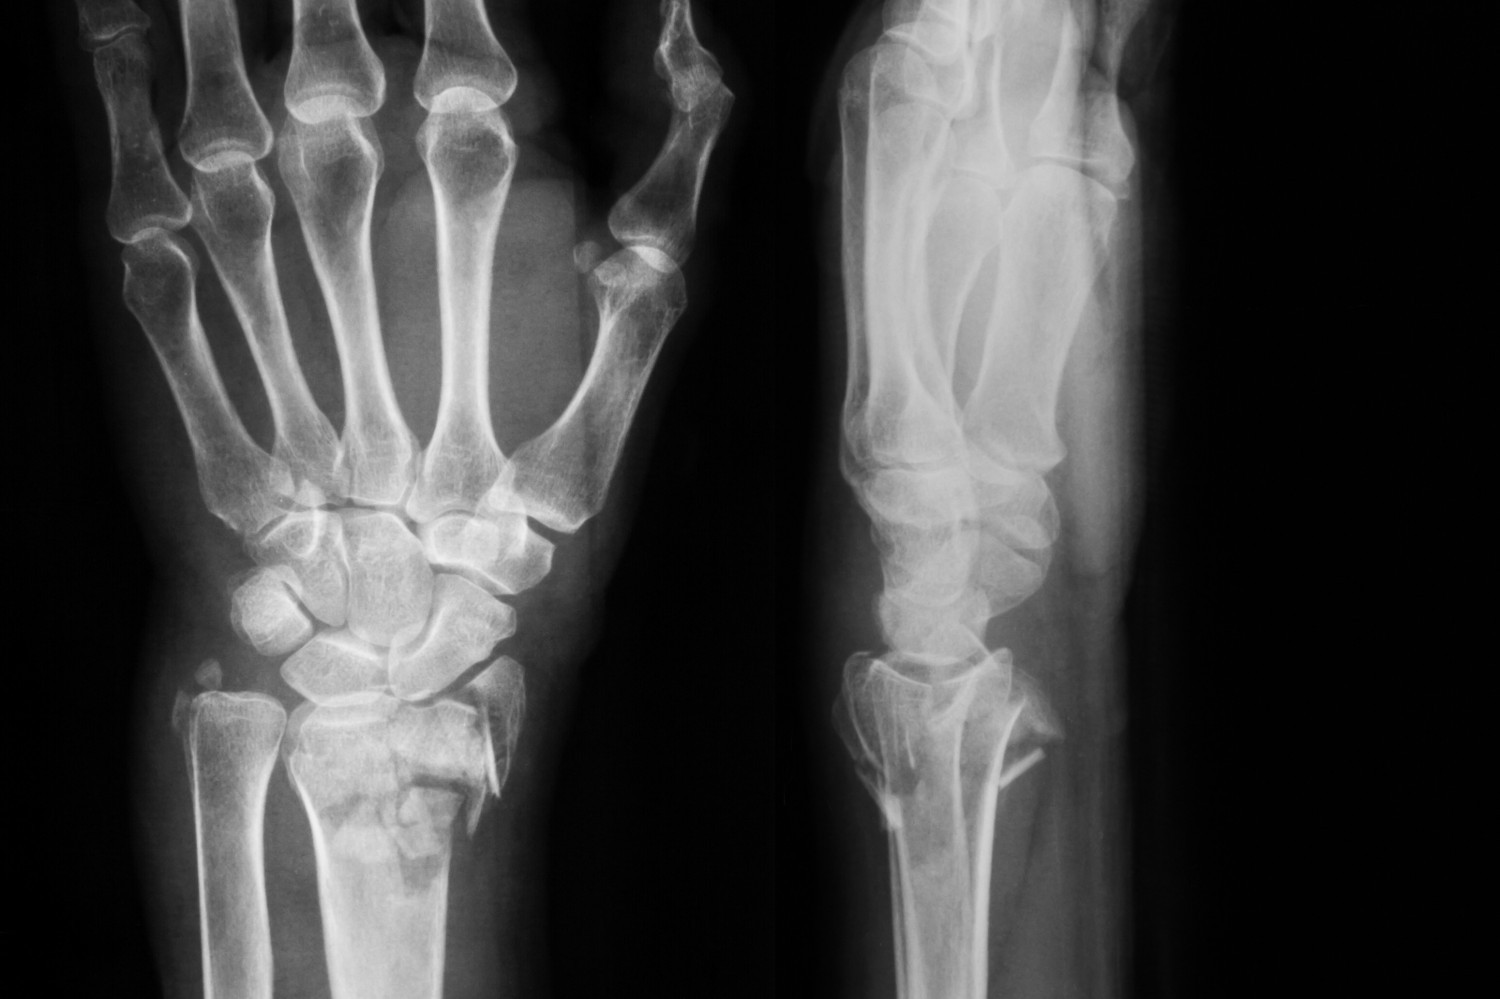

В течение первых двух лет после отмены терапии золедроновой кислотой частота невертебральных переломов увеличилась с 15 до 24 случаев на 1000 человеко-лет. Спустя четыре года частота переломов достигла 42 случаев на 1000 человеко-лет, что соответствовало показателю среди участниц, получавших плацебо.

Частота переломов зависела от минеральной плотности бедренной кости и наличия невертебральных переломов в анамнезе. За четыре года наблюдения минеральная плотность бедренной кости существенно снизилась. После последнего введения золедроновой кислоты этот показатель превышал исходное значение на 4,2%, а в конце исследования – только на 0,8%.

За время дополнительного наблюдения у 92 женщин диагностировали 114 невертебральных переломов.